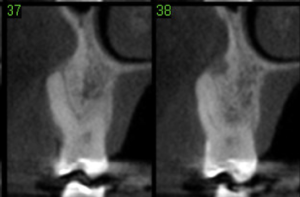

Tomografia pré-operatória.

Tomografia pós-operatória de quatro meses. Notar que aparenta regeneração óssea na região da tábua vestibular e terço cervical sob a membrana.